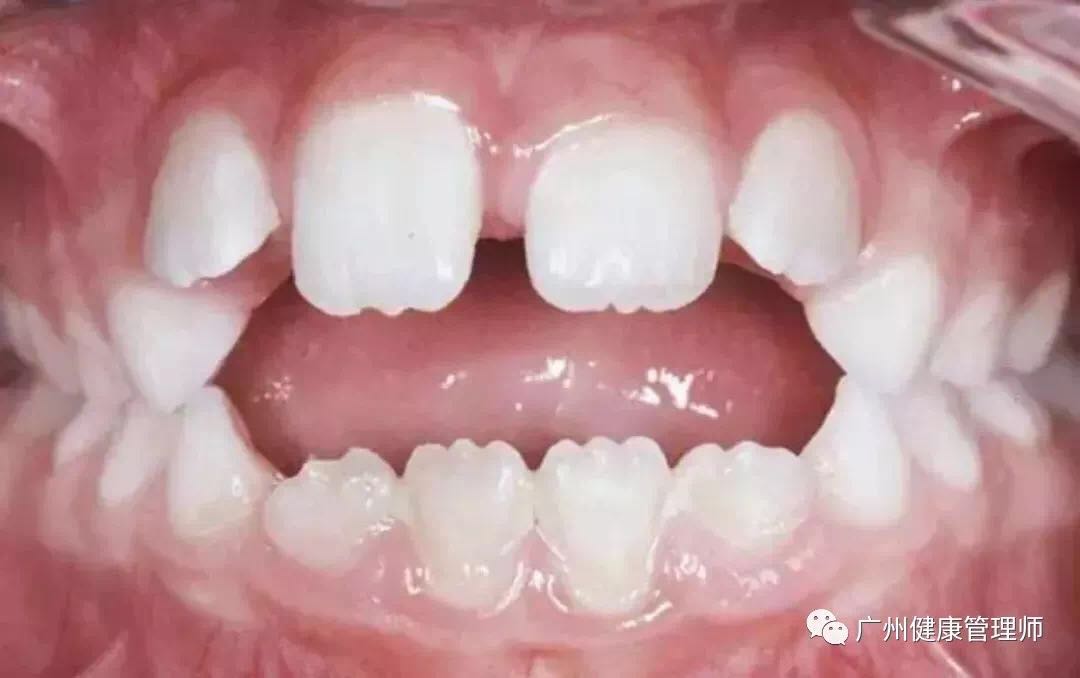

同時,口呼吸時,舌會臥于下頜前牙上,影響前牙垂直向發育,會導致前牙開合。據統計,3-6歲兒童中,口呼吸和前牙開合的關聯率為35.5%。

前牙開頜